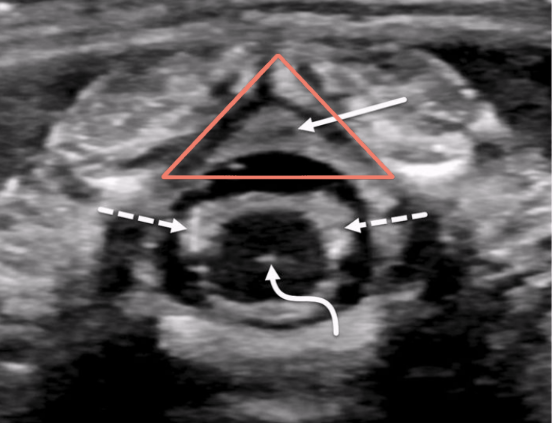

solid white arrow

echogenic epidural fat

vb

vertebral bodies

d

intervertebral disks

p

spinous processes

arrowheads

arachnoid/dural layer

e

epidural space

*

subarachnoid space w/ CSF

sc

hypoechoic spinal cord